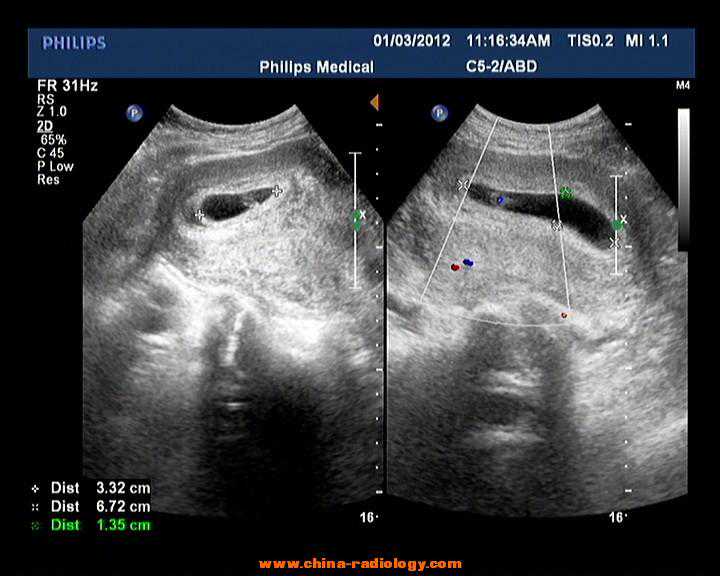

1.孕4-5周:可以看见孕囊,5周左右可以看见原始心管搏动。

2.孕6周时出现胎心搏动,有胎芽,就像是一颗种子才刚刚发芽一样。